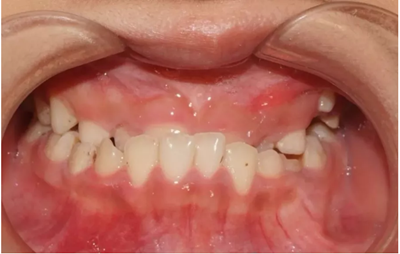

01 反頜

反頜通常被稱為“地包天”,也有些是個別牙反頜。該如何避免?